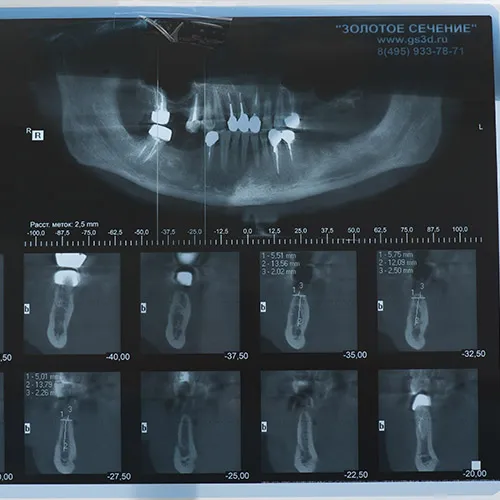

Бесплатная консультация и диагностика

Основная цель нашей клиники - качественная 3D-диагностика чтобы оценить состояние костной ткани и зубов пациента.